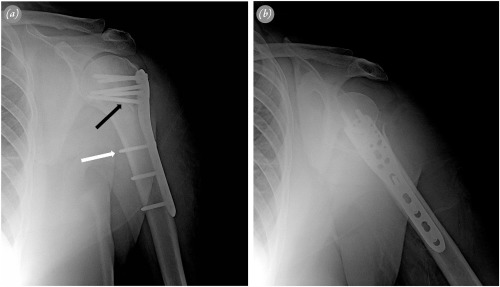

Fig. 2

Fig. 2.

Radiographs of a 57-year-old female patient with 3-part fracture. a. Anteroposterior view with correct positioning of the plate and appropriate screw lengths. A conventional screw (white arrow) was used as a positional screw for indirect reduction, and an inferomedial calcar screw (black arrow) was used to support metaphyseal comminution. b. Lateral view with full internal rotation of the arm.

Sling immobilization was postoperatively used for 1 week, and passive- and active-assisted range of motion exercises were immediately begun. Active exercises were begun after 4 weeks. Radiographic evaluations were routinely performed at 6 weeks, 3 months, 6 months and 1 year, by using 20° external rotation projection for anteroposterior view and full internal rotation projection for lateral view (Fig. 2 ). If suspicion of fracture healing was present at 3 months, radiographic controls were performed more closely. Fracture healing, complications, and head-shaft angle (HSA) were evaluated radiographically. HSA was calculated by the same surgeon (U.G.), according to the method of Hertel et al.17 (Fig. 3 ). An angle above 130° was considered the goal of treatment. Clinical outcomes were assessed at 1 year of follow-up with Constant score. Nerve lesions were assessed clinically.